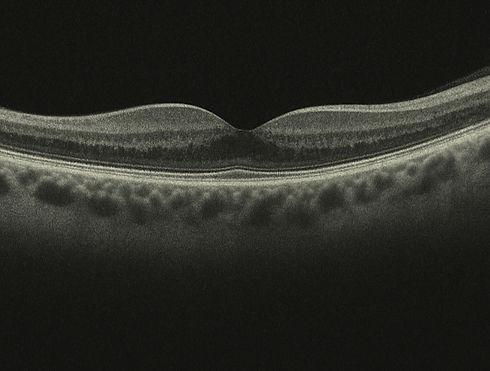

RETINAL IMAGING

Your eye health is our top priority. That's why we offer both retinal photography and OCT (Optical Coherence Tomography) for your exam. Each test gives us a different, but equally important view of your eyes. We can detect eye diseases earlier, track changes over time, and personalize your care and treatment. These tests allow early detection which is key to maintaining lifelong vision.